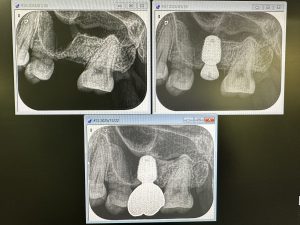

全顎治療の方のインプラントポジショニング決め

仮歯作らないと、位置が決められない

位置決めが非常に重要‼️

20本作成し、シンプラトでプランニングし本決め!

11本埋入予定